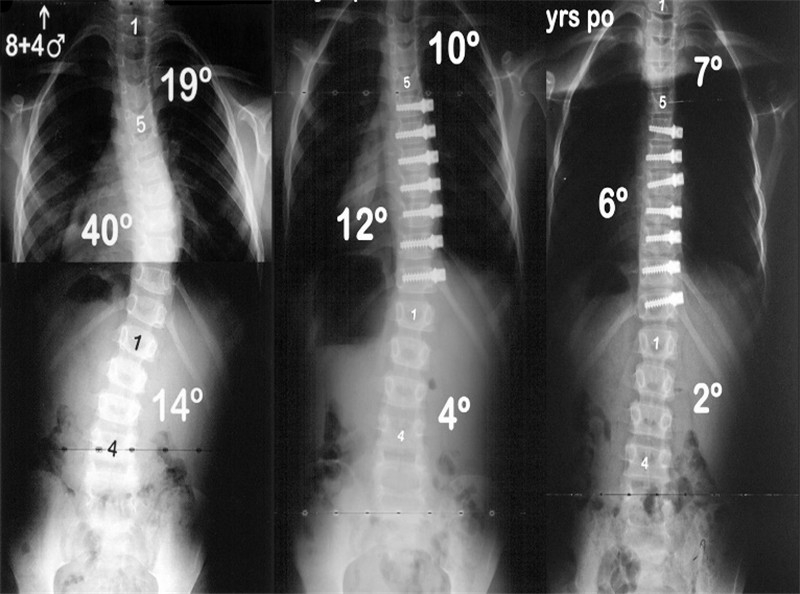

2012年,Akbarnia等[8]报道了MCGR的动物实验及初步临床结果(图 5),实验动物研究中,磁力控制生长棒(magnetically controlled growing rod, MCGR)最终延长达预期80%,且未发现相关并发症。2013年Akbarnia[9]再次报道了14例临床初步结果(图 2 右),平均随访10个月(5.8-18.2),未观察到相关严重并发症,其结果初步验证了其安全性。MCGR相关研究随之成为热点。

图5 左图A:Akbarnia[8]于2012年首次报道MCGR,整个装置包括:带有可延长撑开器的生长棒(B),体外控制伸缩的螺旋磁芯(C)。右图为Akbarnia[9]于2013年报道中的1例5.5岁神经肌肉性EOS患儿。术前正侧位X片(A,B)示右胸弯45°;双棒MCGR术后正侧位X片(C,D);E和F为患儿术后7个月的定期延长后正侧位X片,示T1–T12和T1–S1分别达到12mm和31mm